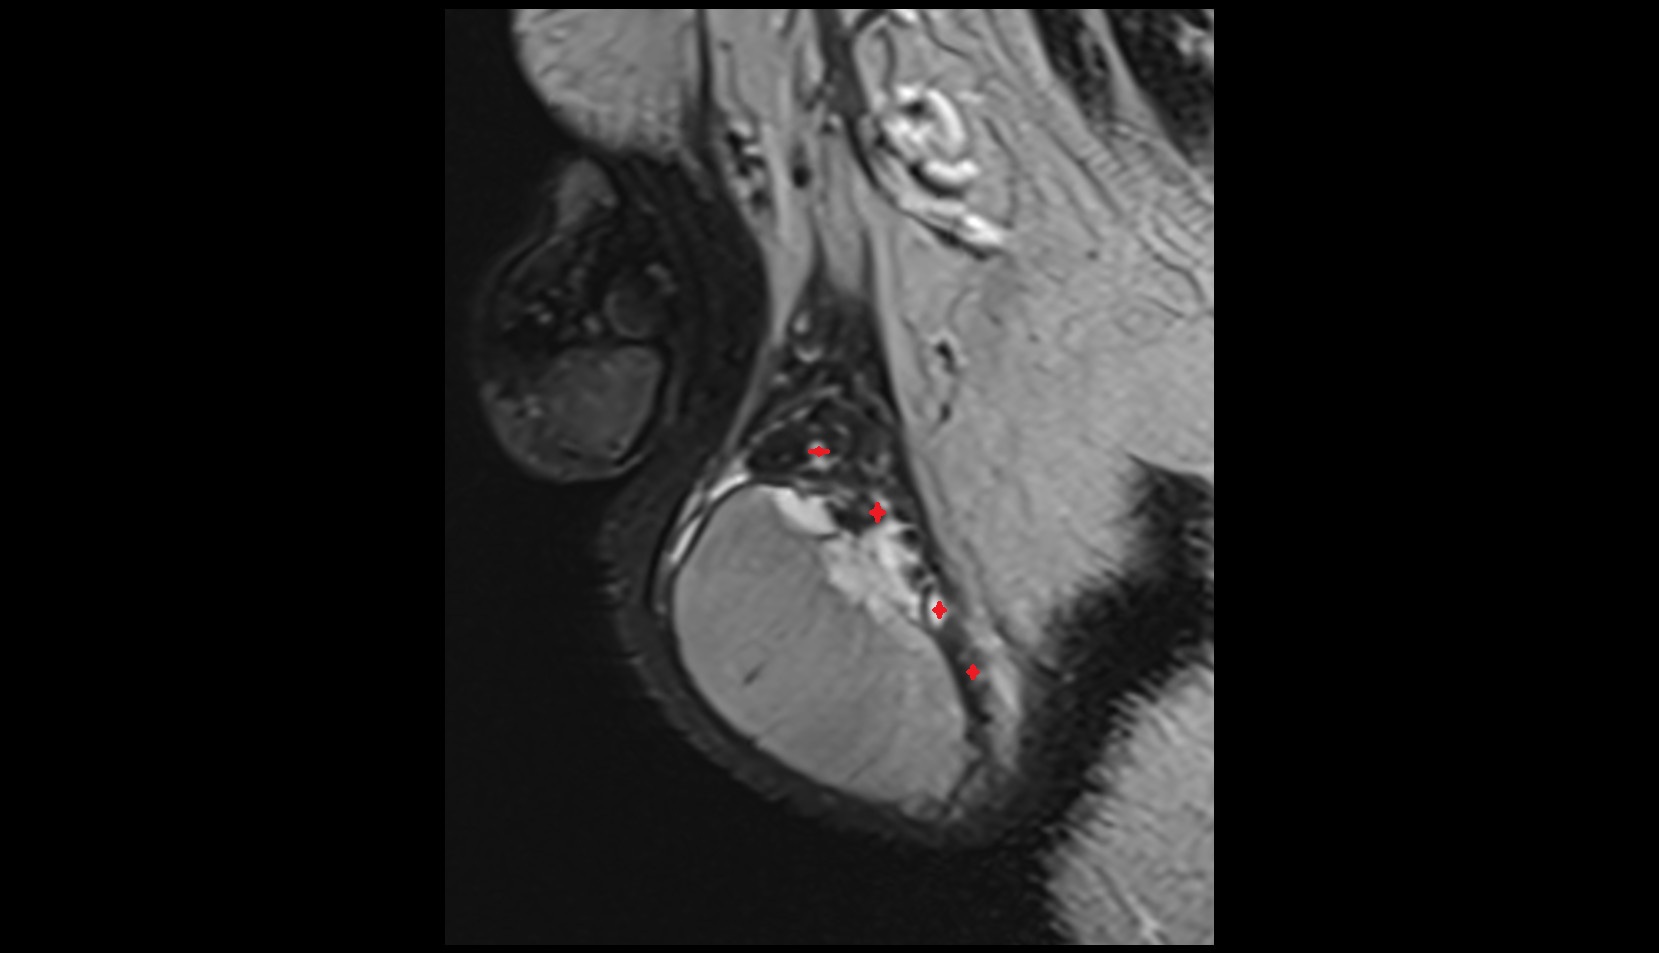

- Peripheral zone of prostate

- Anterior Fibromuscular Stroma of prostate

- Central zone of prostate

- Transitional zone of prostate